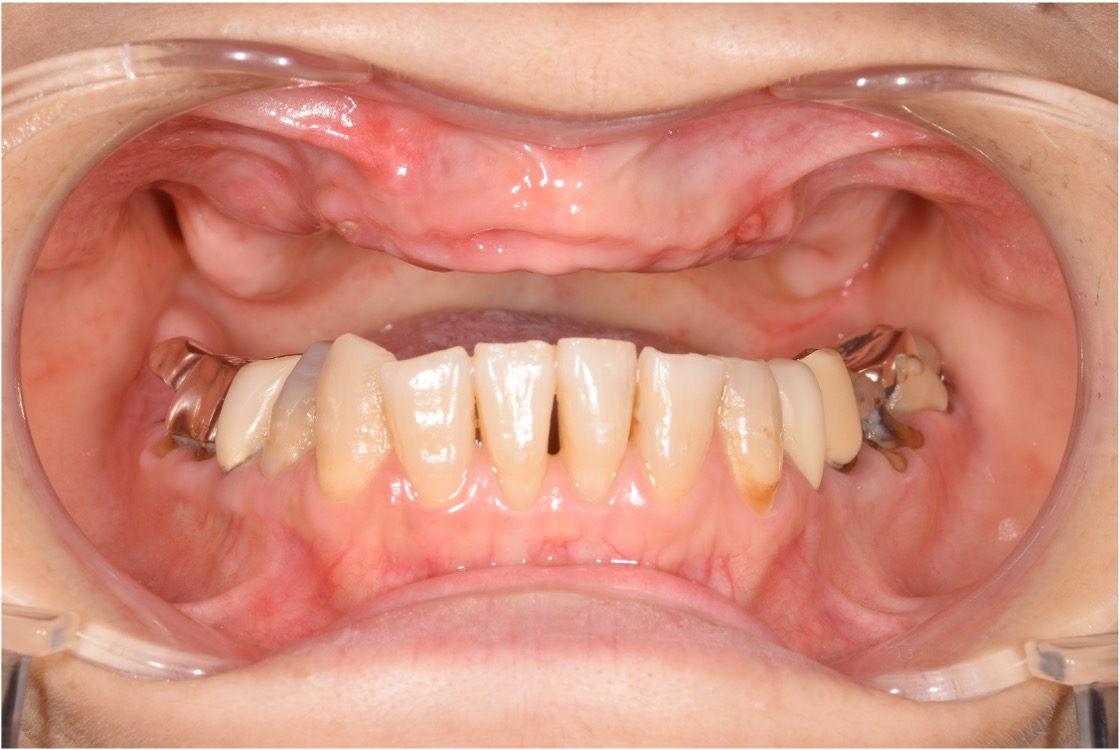

上顎のインプラント埋入

- インプラント手術当日に仮歯を装着することができた。その後安定した後、最終の歯を装着した。

- 固定が弱い場合は手術当日に歯が入れられない可能性があります